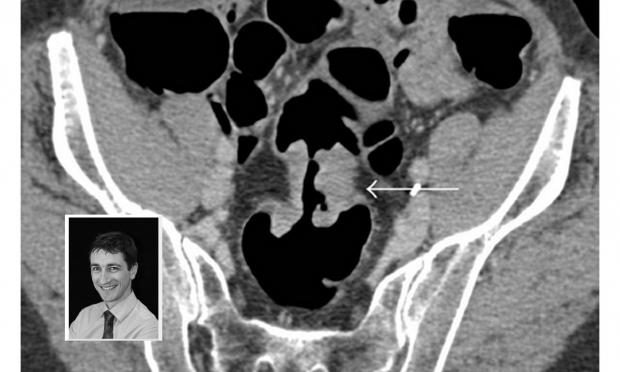

Volume 207, Issue 4: 21 August 2017. Professor Tom Sutherland is a radiologist on the executive of the Abdominal Radiology Group of Australia and New Zealand. He discusses CT colonography and its underuse in Australia. With MJA news and online editor, Cate Swannell.